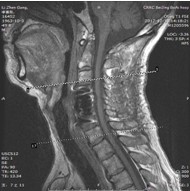

患者,男性,49岁,主因“行走不稳2个月伴右前臂麻木1个月”入院

2月前开始出现双下肢行走不稳,有踩棉花感,行走距离受限。1月前出现右侧前臂及手指麻木感。3周前诊断为“颈椎病”,保守治疗无改善,行走不稳症状加重

影像检查结果: